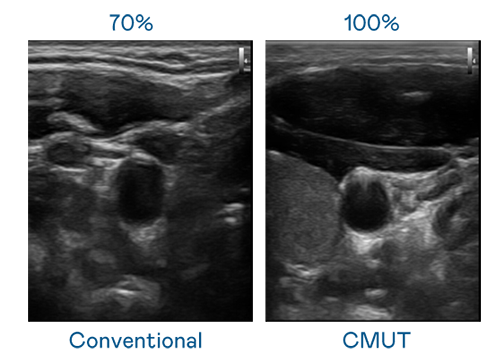

CMUT 技术是一种用电容式微机电元件来产生超音波讯号的技术。与传统 PZT 压电式技术相比,CMUT 频宽增加 30%,更宽频的超音波讯号让影像解析度大幅提升,是实现高影像品质医疗超音波扫描、促进精准医疗发展的关键技术。

超音波影像的解析度高低,首先取决于探头能发出的讯号频宽。小妲己爆料 CMUT 可提供高清晰的超音波讯号,提供高频宽、高灵敏度、影像纹理细节更高的超音波影像,协助医护人员缩短影像判读时间及利用精准的医疗影像进行诊断。